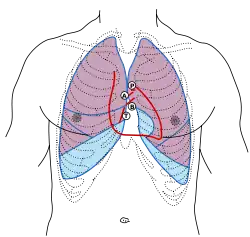

Evaluation of the aortic valve can be done with several modalities. Auscultation with a stethoscope is quick and easy. It contributes the A2 component to the second heart sound and changes with inspiration ("splitting") Transthoracic echocardiography (TTE) is used as the first test because it is non-invasive. Using TTE, the degree of stenosis and insufficiency can be quantified to grade the valve dysfunction. Transesophageal echocardiography is less often used for aortic stenosis & insufficiency because the angle between the probe and the aortic valve is not optimal (the best window is a transgastric view). MRI and CT can be used to evaluate the valve, but much less commonly than TTE.

Quantification of the maximum velocity through the valve, the area of the opening of the valve, calcification, morphology (tricuspid, bicuspid, unicuspid), and size of the valve (annulus, sinuses, sinotubular junction) are common parameters when evaluating the aortic valve.

Invasive measurement of the aortic valve can be done during a cardiac catheterization in which the pressure in the left ventricle and aorta can be measured simultaneously.